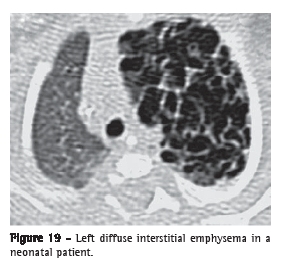

Interstitial emphysema (enfisema intersticial)Interstitial emphysema is characterized by the air dissection of the pulmonary interstitium, typically located on the bronchovascular sheaths, interlobular septa and visceral pleura; it is more frequently identified in neonates receiving mechanical ventilation (Figure 19). Interstitial emphysema is seldom recognized radiographically in adults and is rarely seen on CT scans. The process appears as areas of air density with perivascular distribution, peribronchovascular distribution or distributed along the interlobular septa (Figure 20), or as rounded areas of low attenuation simulating small bullae or cysts (Figures 19 and 20).(40,41)